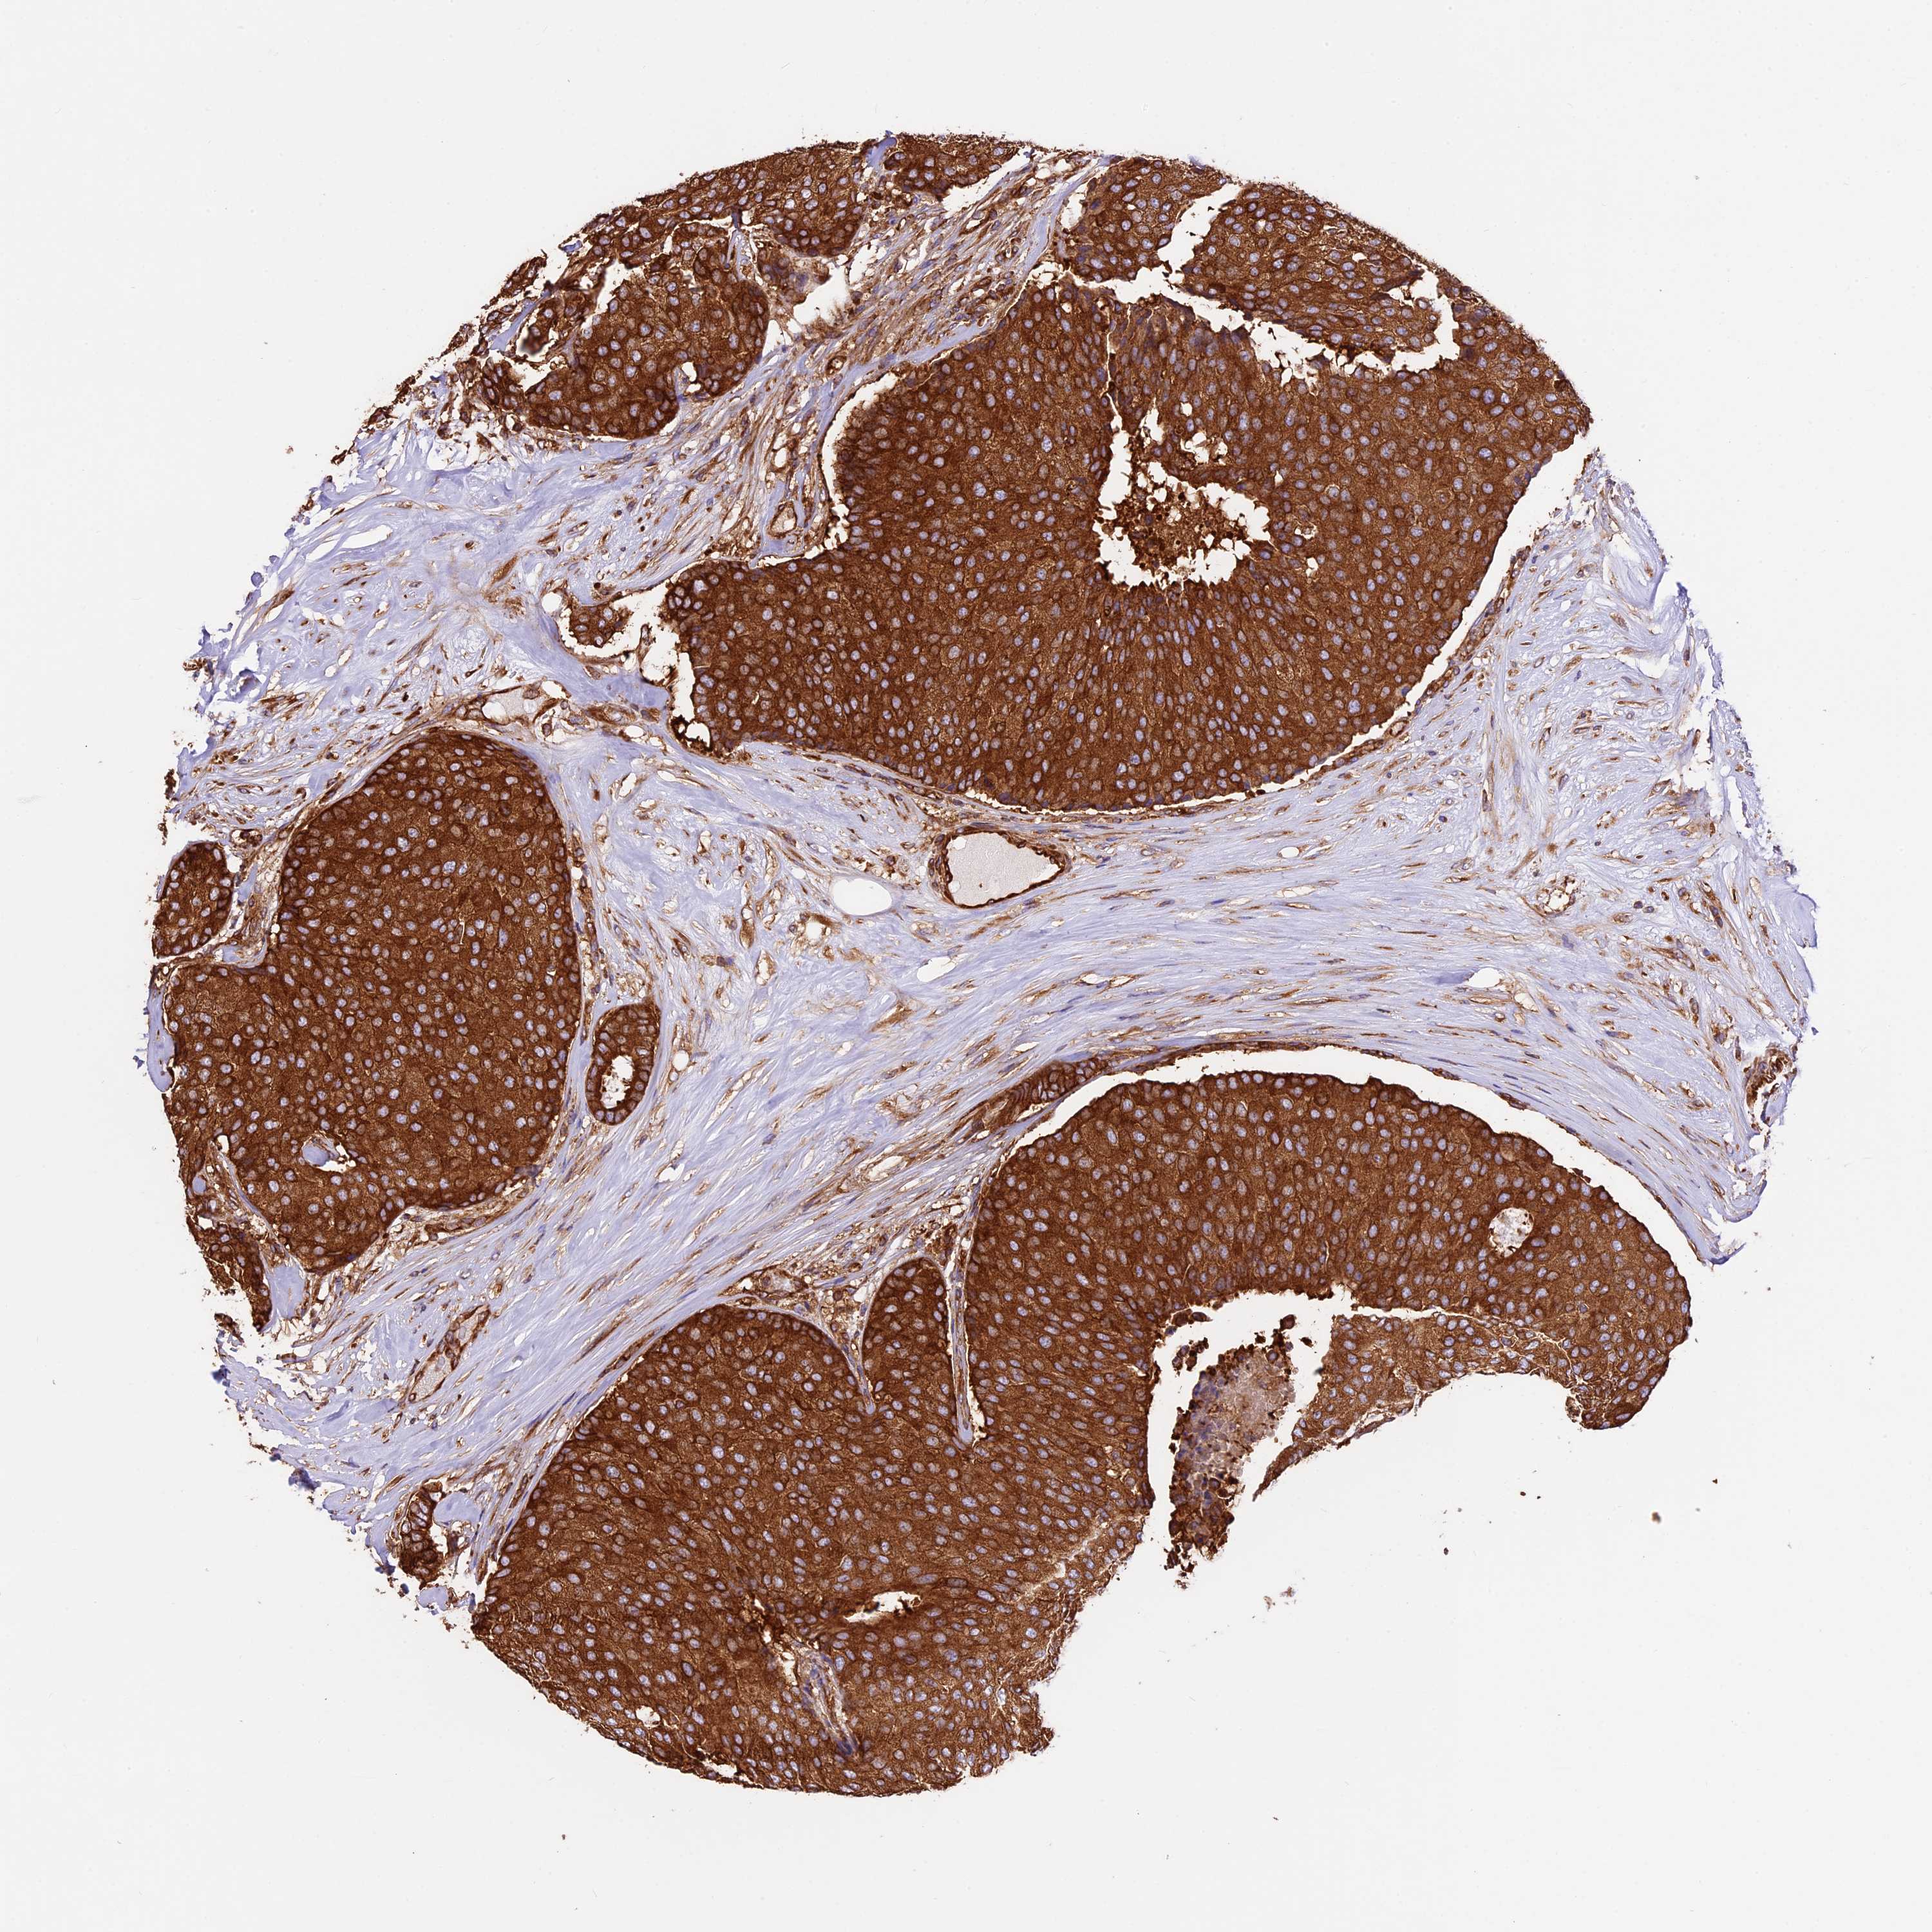

CANCER BREAST CANCER Show tissue menu

BRCA TCGA BRCA VALIDATION PROTEIN EXPRESSION

Breast cancer

Human cancer